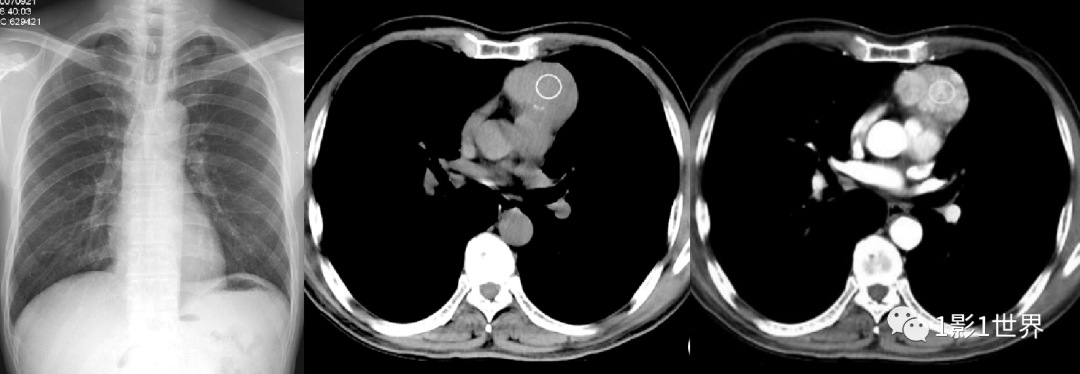

图片左图,胸部X线片,正常纵隔表现。后两幅图为前纵隔胸腺瘤,CT平扫+增强图像,显示肿瘤部位、大小。

最后结果是上纵隔胸腺瘤,胸腺在青春期大部分退化,残留的一些胸腺组织,可以发生异常增生,形成肿瘤,大多数是良性的,生长缓慢,较大时,引起纵隔形态改变,X线片上表现为上纵隔增宽,胸部CT可以发现,在胸腺特定的部位,异常组织,诊断并不困难。